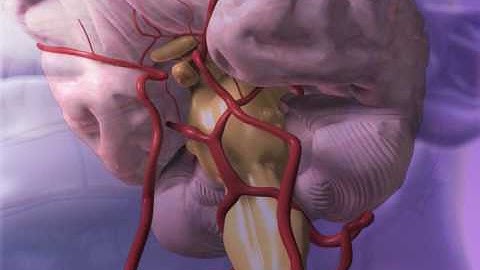

Extradural vs Subdural Haematomas | How do we Diagnose them on CT?